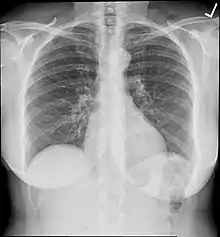

In medical imaging, an anti-scatter grid (also known as a Bucky-Potter grid) is a device for limiting the amount of scattered radiation reaching the detector,[1][2] thereby improving the quantity of diagnostic medical x-ray images. The grid is positioned on the opposite side of the patient from the x-ray source, and between the patient and the X-ray detector or film. Reducing the amount of scattered x-rays increases the image's contrast resolution, and consequently the visibility of soft tissues.

Scattered x-rays do not travel in parallel to rays that pass directly through the patient. The quantity of scattering depends on several factors including: x-ray beam area, x-ray photon energies (determined by tube voltage setting), thickness of the tissue, and the composition of the tissue.[4] By 'rejecting' scattered x-rays before they reach the detector, the Bucky-Potter grid improves recorded contrast.

Grids are used particularly in examinations where a large quantity of scatter is created, i.e., those involving a large volume of tissue being irradiated and those requiring low energy i.e. voltage. The scatter would otherwise degrade the image by reducing the contrast and resolution. Use of a grid, however, requires a greater radiation exposure to the patient as a good deal of primary beam is also attenuated by the lead slats, and for this reason grids are not used for all examinations, particularly in pediatric practice.